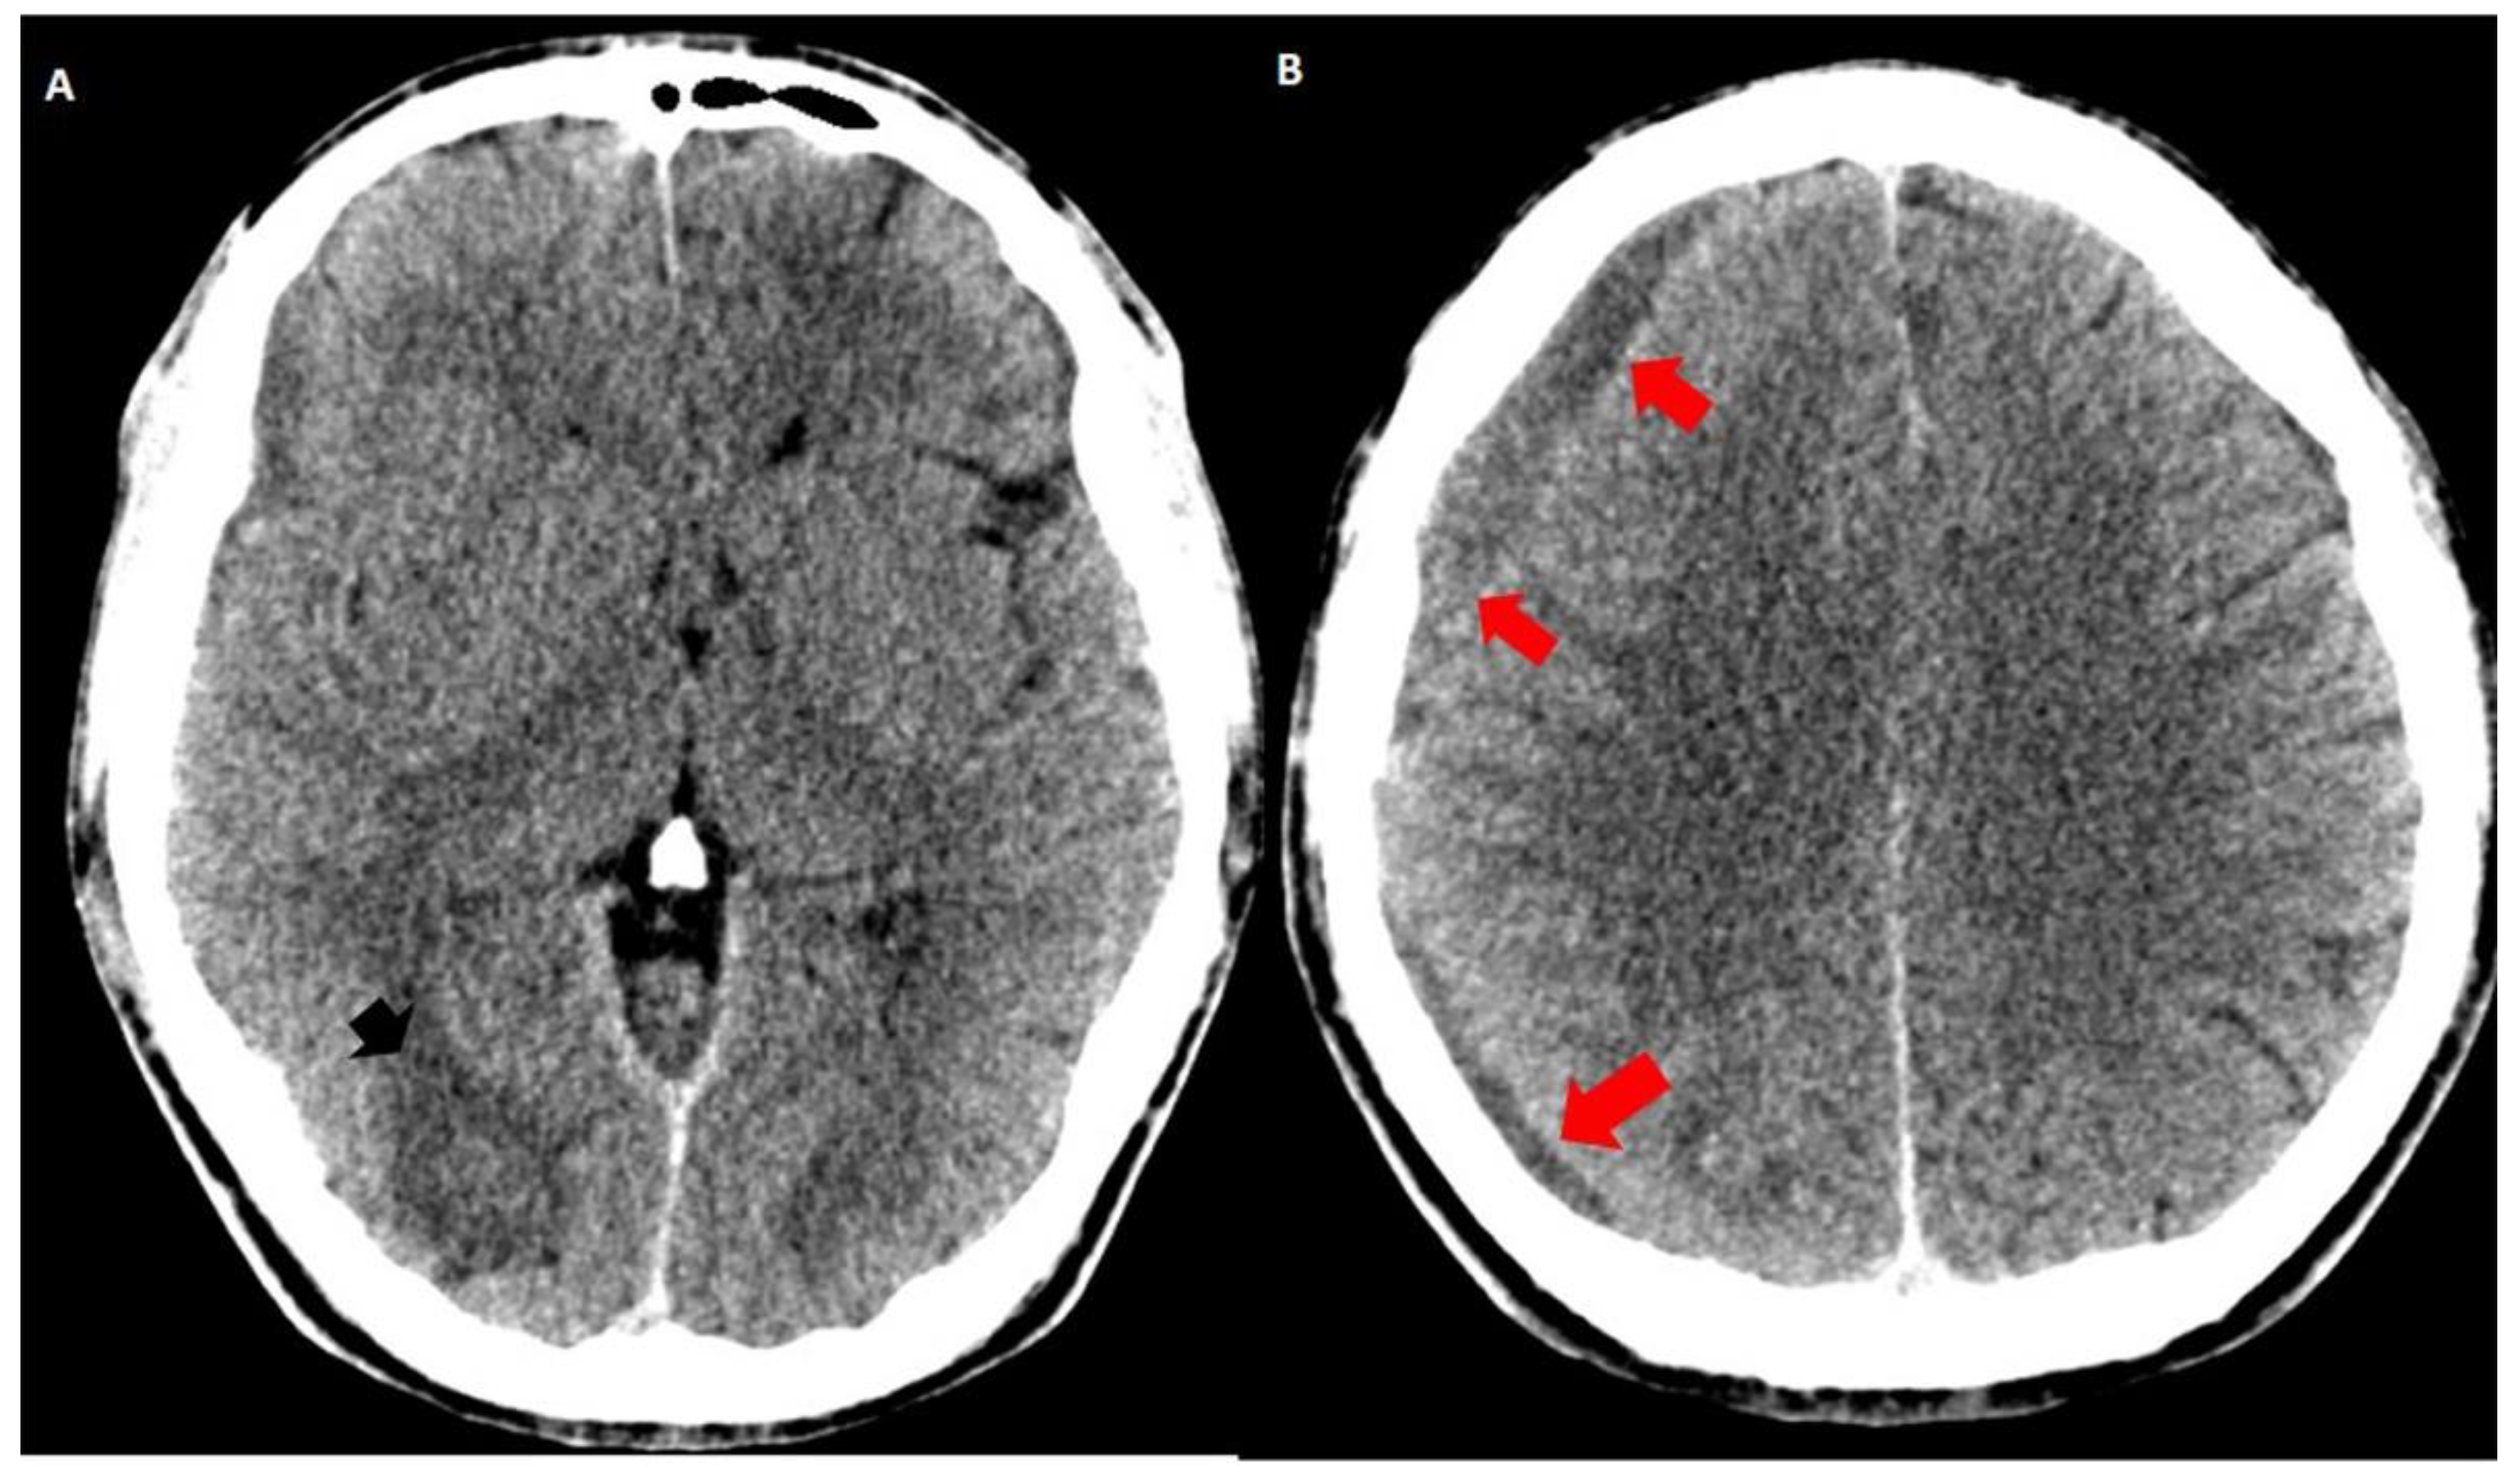

Both hematomas were reabsorbed gradually (Figure 2), with satisfactory clinical evolution after a two-month follow-up period. Figure 2 shows the increased frontal subdural hematoma and its extension to parietal and frontal lobes. Angiography revealed ecstatic cortical veins, one of them with saccular dilatation adjacent to the IPH (Figure 3). For this reason, we decided to perform cerebral angiography, which confirmed the dural arteriovenous fistula. It connected the artery, a branch of the external carotid artery, with cortical veins in the superior sagittal sinus drainage (Figure 4). After endovascular therapy, the evolution of the patient was satisfactory (Figure 5 and Figure 6). Two years later, no bleeding had appeared, and the subsequent angiographic studies were negative.

Figure 2.

Simple brain CT one month later: the increased hypodensity of the intraparenchymal (black arrowhead in (A)) and subdural hematomas (red arrows in (A,B)) indicate hemoglobin degradation. The frontal subdural hematoma slightly increased its volume and extended to the right parietal region (red arrows).